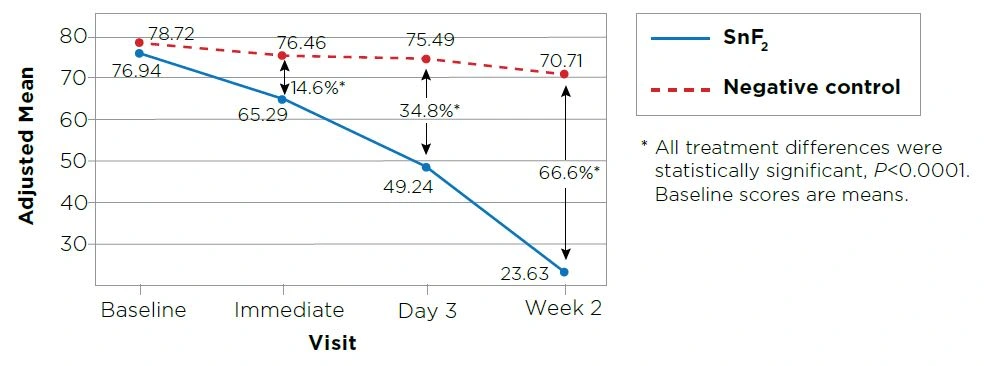

The stannous fluoride (SnF2) dentifrice provided superior sensitivity protection relative to the negative control immediately after the first use based on the Thermal Schiff Index (13.8%, P<0.0001) and the Thermal Air Visual Analog Scale (14.6%, P<0.0001). See Figures 1 & 2.

The SnF2dentifrice also provided superior (P<0.0001) relief relative to the negative control at Day 3 and at Week 2 based on the Thermal Schiff Air Index (31.8% and 61.3%, respectively), the Thermal Air Visual Analog Scale (34.8% and 66.6%, respectively) and the Tactile Yeaple Probe (186% and 239%, respectively). See Figures 1 & 2 and Table 1.

Figure 1. Thermal Schiff Air Index Adjusted Mean Scores (Lower score indicates less sensitivity)

Figure 2. Thermal Air Visual Analog Scale Adjusted Mean Scores (Lower score indicates less sensitivity)